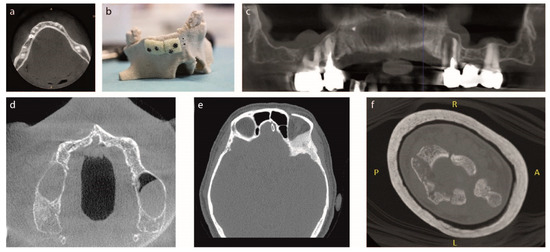

- Case #1: The first patient, 60-year-old female, showed hypodontia in the lower dental arch (three teeth in region 45, 46, 47 missing) and lack of a bone portion at diagnosis by Cone Beam CT (a.k.a. CBCT) (Figure 1a). Since a greater amount of bone was needed to carry out the dental implant, she underwent bone grafting with custom manufactured SBoD. The operating technique required a horizontal and vertical augmentation: bone defect did not have a simple shape, so a customized graft was required. By 3D reconstruction a model of the patient’s mandibular bone was generated first, and then the missing bone component was designed (Figures S1 and S2 in Supplementary Materials). The missing pieces were also tested on a stereolithographic model. The surgical operation required an engraving into the gum to reach the alveolar bone. Next, the custom-made pieces of SB were positioned in the area where an increase of the amount of bone was needed. When the right position for the bone graft was found, it was fixed with screws, to allow the tight anchoring of the graft to the patient receiving bone. Furthermore, in the procedure of soft tissue closure over the implant, good care was taken to release the tissue flaps proximally using an elevator to obtain a tension free flap.

- Case #2: The second patient, 57-year-old female, smoker, showed partial edentulia and lack of bone and teeth from 21 to 27 throughout the upper right dental arch, as diagnosed by CBCT. The patient’s jaw was rebuilt based on CT and surgeon cut SB standard blocks on a sterile 3D model of the patient’s anatomy (Figure 1b). A “periosteal elevation” was further performed, a procedure by which the periosteum together with the soft tissues is removed from the bone, to allow the positioning of the customized SB graft. The custom-made block grafts were implanted within the bone defect area. Screws in the bone stabilized the graft. After checking the stability of the system and having the screws firmly positioned, the incision was sutured; soft tissues covered the bone graft, and the two gum flaps were sutured.

- Case #3: The third patient, 59-year-old female, showed severe edentulia with only two teeth left on the upper arch, at diagnosis by CBCT (Figure 1c). This loss of teeth has led to bone reabsorption, and, thus, the lack of bone portion was deep. She underwent surgery, after custom made SBoD blocks were obtained. A periosteum elevation procedure was performed, as previously described. Additionally, before placing the graft in the bone defect area, the surface of the bone was micro-drilled to induce bleeding intending to further enhance the regenerative processes (a.k.a. micro-channeling practice). Then, the bone graft was implanted and stabilized by screws. After checking the stability of the system and having the screws firmly positioned, the dentist deposited an autologous platelet concentrate (PRP) to promote tissue healing. Lastly, the bone graft was covered by soft tissues. and the two flaps of the gum were sutured.

- Case #4: The fourth patient, 57-year-old male, showed four different bone defects as diagnosis by CBCT (Figure 1d). The periosteum disconnection procedure was performed, as described in previous cases. Once the bone was reached, the surgeon customized by hand SB standard blocks, that were implanted and firmly stabilized by screws. As in previous cases, the wound was finally closed on all its levels till external gums.

- Case #5: The fifth patient, 65-year-old female, showed a meningioma tumor located at the back of the right eye, diagnosed by CT (Figure 1e). The tumor included temporal and sphenoid bone in the skull. The surgical operation involved the removal of the tumor as well as part of two bones, which were rebuilt with custom-made SBoD grafts (Figure S3 in Supplementary Materail). CT was used to design surgery, both in terms of tumor rescission and further bone reconstruction. Given the wide extension of the tumor mass, a significant portion of bone had to be removed, and custom-made SB was provided in pieces, which were assembled during surgery, bed-side, and soaked into blood before grafting, to accelerate the osteointegration process [35]. Once placed, the complete graft has been stabilized with two small titanium plates (KLS-Martin, Germany).

- Case #6: The sixth case, 65-year-old male, presented a clear lack of bone in the distal left radial epiphysis of the left hand, at diagnosis by CT. For a better design of bed-side hand customized SB standard blocks, a 3D model where the bone defect was visible at the apex of the radial bone was built (Figure 1f). The surgical operation required the insertion of the SB block inside the defect during stabilization.